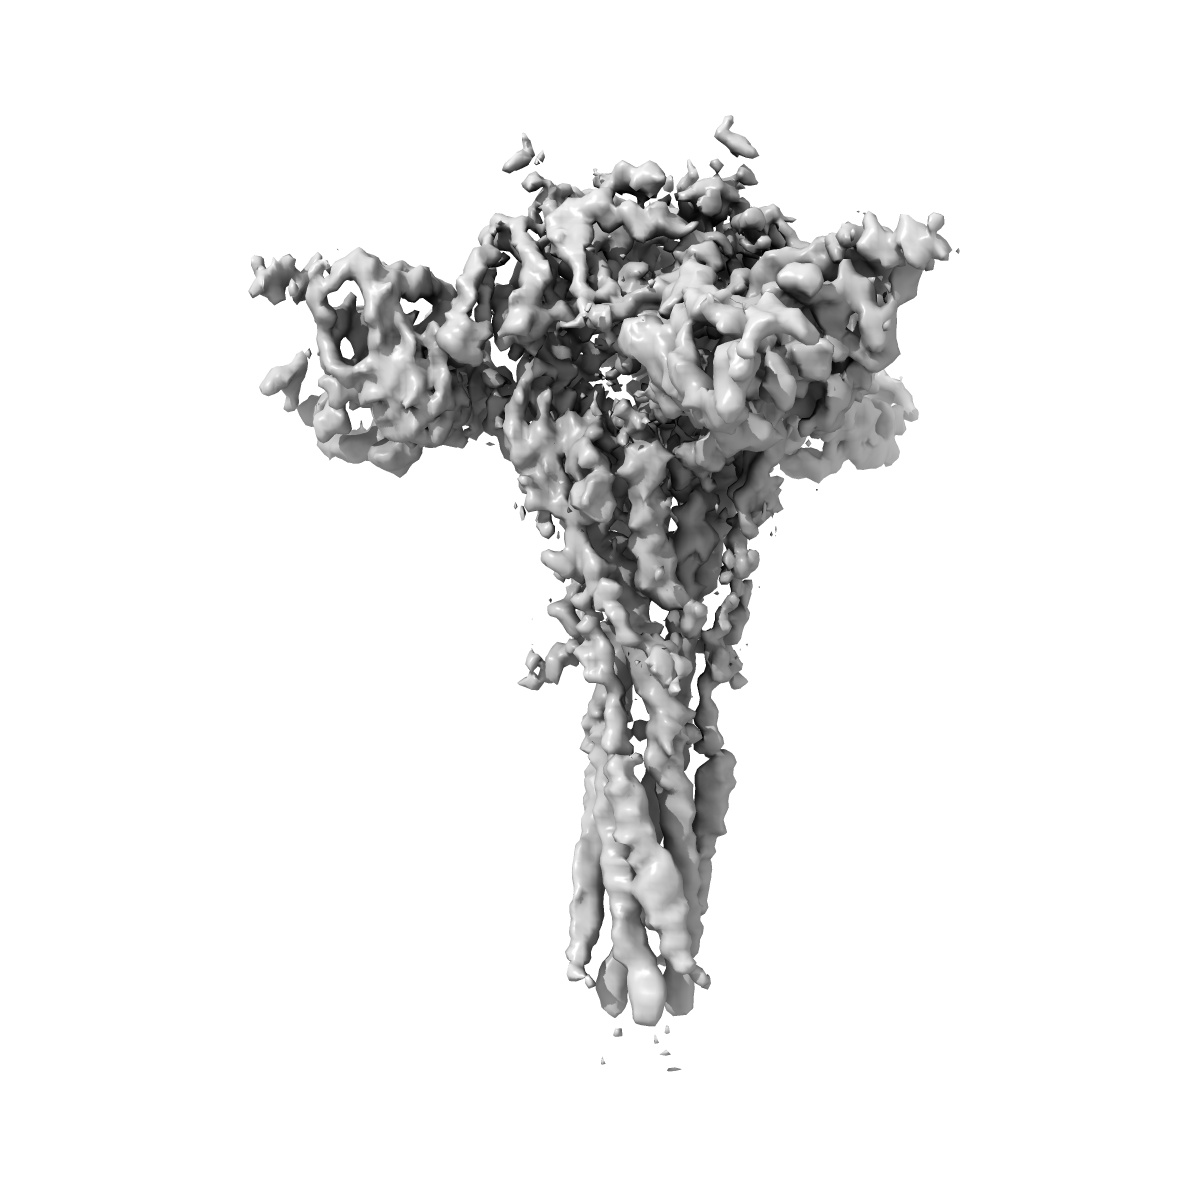

3.9A Cryo-EM structure of murine antibody bound at a novel epitope of respiratory syncytial virus fusion protein

EMD-7774

Single-particle

3.9 Å

Sample Organism: Mus musculus, Human respiratory syncytial virus A2, Human immunodeficiency virus 1

Sample: Complex of R4.C6 Fab with RSV F protein

Fitted models: 6cxc

Deposition Authors: Xie Q, Wang Z

Structure basis of neutralization by a novel site II/IV antibody against respiratory syncytial virus fusion protein.

Xie Q, Wang Z, Ni F, Chen X, Ma J, Patel N, Lu H, Liu Y, Tian JH, Flyer D, Massare MJ, Ellingsworth L, Glenn G, Smith G, Wang Q

(2019) PLoS One , 14 , e0210749 - e0210749